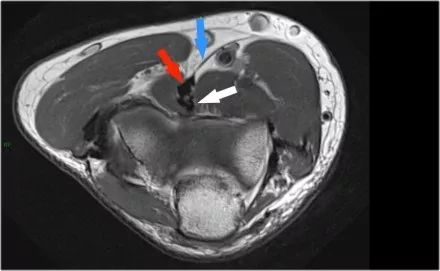

在研究韧带时,尤其是UCL,始终使用轴向图像。如果你看内侧上髁,你会发现后束是一个薄的结构(蓝色箭头)。注意在肘管内的尺神经。

后束形成肘管隧道的地板。支持带覆盖肘管。请注意,前束更厚(白色箭头)。您可以看到前韧带和后韧带之间的区别,即使它们形成一条韧带。走向远端,我们会看到它们合并在一起以附着于崇高的结节。

下面的图像,请注意,前束是完整的,并牢固地附着在崇高的结节上(黄色箭头)。在接下来的两张图像上,有一些软组织水肿,后面有更多异常信号(红色箭头)。所以我们怀疑后束的病理学。现在你记得轴向图像可能会有所帮助。

在下面轴向图像上,我们很好地看到前束是o.k. (红色箭头)。它旁边只有一些水肿。

然而,后束不是o.k,有一部分撕裂。这种情况我们偶尔会在投掷运动员中看到,前束完整,肘部不稳定。他们以某种方式撕裂了他们的后束,导致疼痛。他们不需要手术,但它仍然可能让他们在游戏中停留很长一段时间。